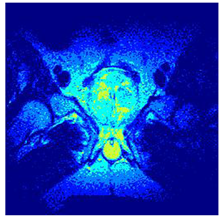

| Image | nt = 3 | nt = 4 | nt = 5 | nt = 8 |

|---|---|---|---|---|

| 1 | ![]() | ![]() | ![]() | ![]() |

| 2 | ![]() | ![]() | ![]() | ![]() |

| 3 | ![]() | ![]() | ![]() | ![]() |

| 4 | ![]() | ![]() | ![]() | ![]() |

| 5 | ![]() | ![]() | ![]() | ![]() |

| 6 | ![]() | ![]() | ![]() | ![]() |

| 7 | ![]() | ![]() | ![]() | ![]() |

| 8 | ![]() | ![]() | ![]() | ![]() |

| 9 | ![]() | ![]() | ![]() | ![]() |

| 10 | ![]() | ![]() | ![]() | ![]() |

| 11 | ![]() | ![]() | ![]() | ![]() |